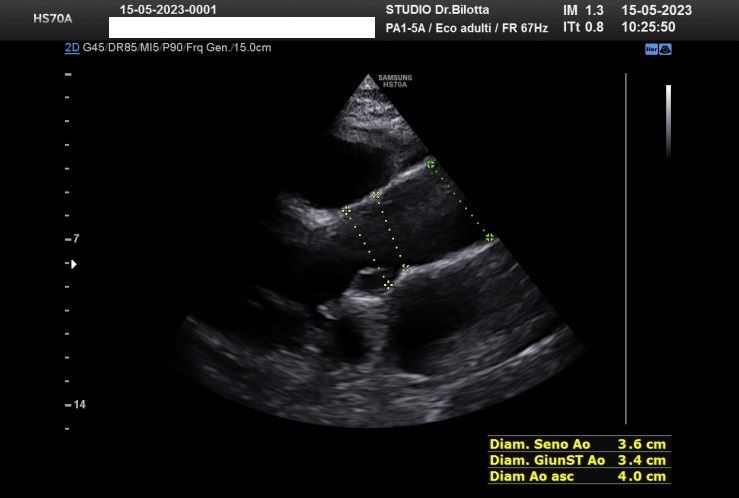

Diploma di maturità classica. Laurea in Medicina e Chirurgia con Lode a 26 anni. Specialista in Oncologia Generale Diagnostica e Preventiva con Lode a 31 anni. Specialista in Malattie Cardiovascolari a 36 anni. Medico generalista dal 1990 poi ospedaliero per trent'anni dal 1993 al 2022 nel corso dei quali ho refertato oltre 100 mila tracciati elettrocardiografici, effettuato oltre 30 mila consulenze specialistiche, praticato circa 10 mila esami ecocardiografici, condotto oltre 2 mila test ergometrici sia su cicloergometro che su treadmill, visionato circa 1500 esami Holter Ecg e ABP ( Ambulatory Blood Pressure ) occupandomi prevalentemente di prevenzione cardiovascolare, ipertensione arteriosa, cardiopatia ischemica, valvulopatie. Dal 2023 ho deciso di trasferire le mie competenze nella libera professione presso il mio studio privato che è stato allestito in linea alle moderne esigenze tecnologiche. Metodiche diagnostiche attualmente praticate: Elettrocardiografia a riposo, Ecocardiografia mono-bidimensionale, PW, CW, Colordoppler tridimensionale, GLS Strain Speckle tracking, Monitoraggio Holter Pressorio delle 24 ore, Monitoraggio Holter ECG 12 canali dinamico delle 24 ore.

Foto e video